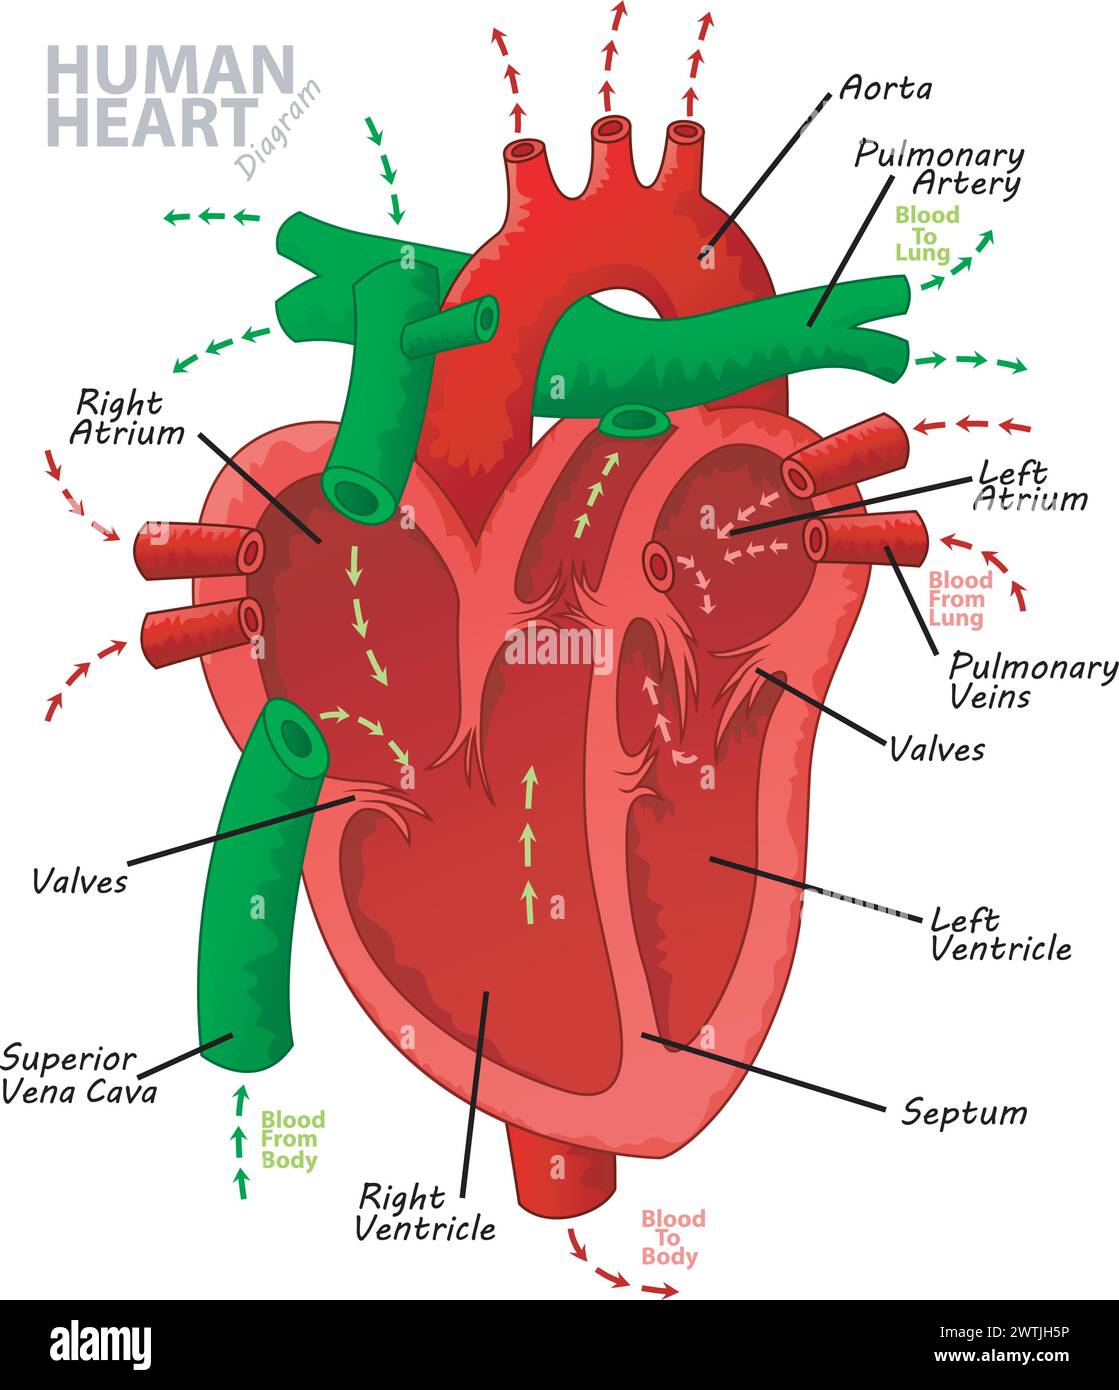

Anatomy of the human heart. Cross sectional diagram of the heart with main parts labeled. Human heart diagram Vector illustration. Educational diagram Stock Vectorhttps://www.alamy.com/image-license-details/?v=1https://www.alamy.com/anatomy-of-the-human-heart-cross-sectional-diagram-of-the-heart-with-main-parts-labeled-human-heart-diagram-vector-illustration-educational-diagram-image551609872.html

Anatomy of the human heart. Cross sectional diagram of the heart with main parts labeled. Human heart diagram Vector illustration. Educational diagram Stock Vectorhttps://www.alamy.com/image-license-details/?v=1https://www.alamy.com/anatomy-of-the-human-heart-cross-sectional-diagram-of-the-heart-with-main-parts-labeled-human-heart-diagram-vector-illustration-educational-diagram-image551609872.htmlRF2R1C00G–Anatomy of the human heart. Cross sectional diagram of the heart with main parts labeled. Human heart diagram Vector illustration. Educational diagram

Human Heart Diagram Anatomy, Vector Illustration Stock Vectorhttps://www.alamy.com/image-license-details/?v=1https://www.alamy.com/human-heart-diagram-anatomy-vector-illustration-image600312882.html

Human Heart Diagram Anatomy, Vector Illustration Stock Vectorhttps://www.alamy.com/image-license-details/?v=1https://www.alamy.com/human-heart-diagram-anatomy-vector-illustration-image600312882.htmlRF2WTJH5P–Human Heart Diagram Anatomy, Vector Illustration